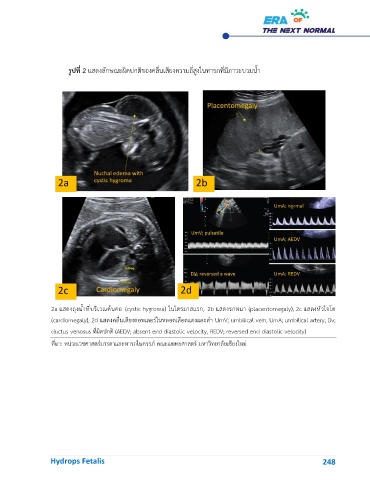

รูปที่ 2 แสดงลักษณะผิดปกติของคลื่นเสียงความถี่สูงในทารกที่มีภาวะบวมน้ำ

2a แสดงถุงน้ำที่บริเวณต้นคอ (cystic hygroma) ในไตรมาสแรก, 2b แสดงรกหนา (placentomegaly), 2c แสดงหัวใจโต

(cardiomegaly), 2d แสดงคลื่นเสียงดอพเลอร์ในหลอดเลือดแดงและดำ UmV; umbilical vein, UmA; umbilical artery, Dv;

ductus venosus ที่ผิดปกติ (AEDV; absent end diastolic velocity, REDV; reversed end diastolic velocity)

ที่มา: หน่วยเวชศาสตร์มารดาและทารกในครรภ์ คณะแพทยศาสตร์ มหาวิทยาลัยเชียงใหม่